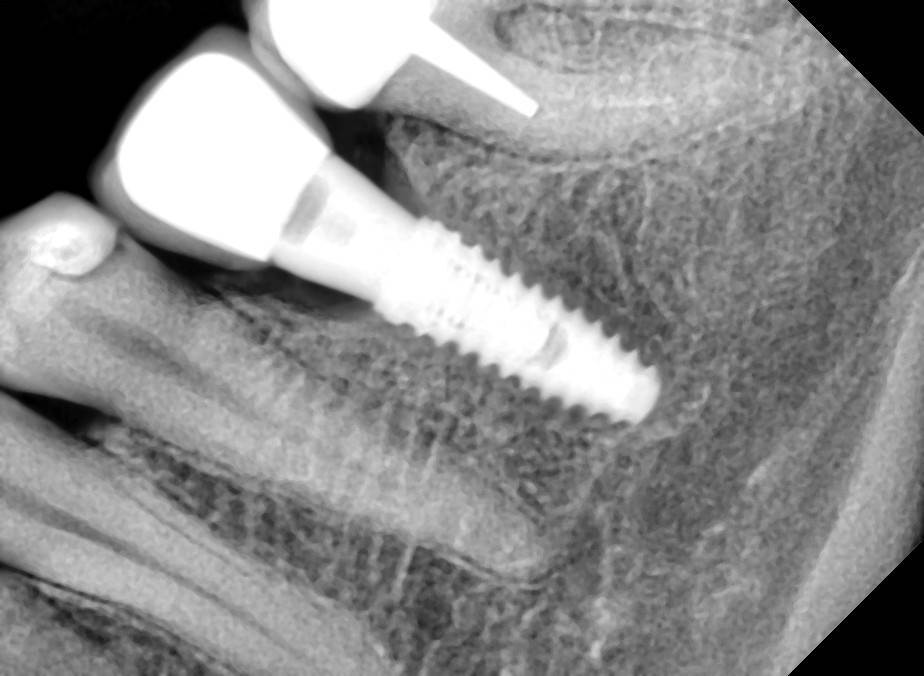

Fin Опубликовано 23 мая, 2022 Поделиться Опубликовано 23 мая, 2022 19 часов назад, Женька сказал: на суперлайнах вообще почти не падает от такой игры) да, это уже знаю) научен горьким опытом резорбции на 2-3 витка) В потому что основной торк у Вас на шейке импланта в таких случаях возникает. В Моей практике Шаг назад и два вперед работает и в кортикальной ткани если очень долго это делать.Например если получаю гиперторк на последнем мм, не убираю имплант а продолжаю рабоать с другим и возвращаюсь к нему через 2-3 минуты (шаг назад и два вперед) потом снова и снова. Можно пройти метчиком кортикальную ткань или следующим размером сверла. Кость над платформой можно убрать бон профайлером если его нет, беру приямой наконечник с двердосплавным бором 200-300 об с макс охлаждением. От себя советую всегда делать снимки после установки формиков (и на ВЧ и на НЧ) часто в кость упираются а мы думаем что прикрутили. 19 часов назад, Aquarius сказал: Собственными глазами видел на собственном винте не то что восстановление резорбции в 3 витка после гиперторка , но и гиперрост кости после 3-х летней функции. Вот и пойми эти импланты. Линкявичуса читаю, чтобы понять По поводу восстановления кости. Импланты поставлены около 6 лет назад. Конечно я понимаю что сейчас допустил много ошибок ,но вот у платформы 3.5 кость даже наросла. И второй случай, не такой показательный конечно, но факт. 1 снимок на момент примерки каркаса, мерял с другой стороны мостик и заодно примерил и эту коронку Ссылка на комментарий

Aquarius Опубликовано 27 мая, 2022 Поделиться Опубликовано 27 мая, 2022 (изменено) 2016 г - установка имплантов. В то время находился под впечатлением от исследований Карлоса по гиперторку. Дал под сотню на дистальном импланте . Потом сильно пожалел))) Второй снимок - спустя 4 года на осмотре. https://wampi.ru/image/RZ3XaNg https://wampi.ru/image/RZ3XLcn Изменено 27 мая, 2022 пользователем Aquarius Ссылка на комментарий